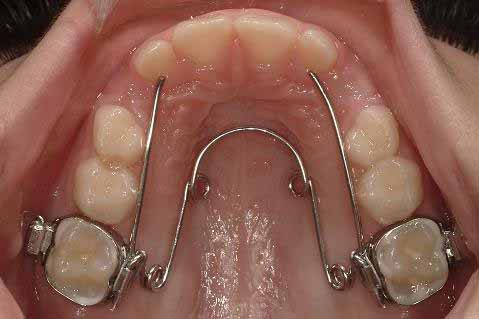

混合歯列期または後期の乳歯列期における片側性交叉咬合の治療は、通常、クワドヘリックス(画像2)または拡張床(画像3)を用いて行われます。

- クワドヘリックスは、拡張床よりも優れた、非常に効果的な治療法です。

- クワドヘリックスまたは拡張床のいずれかを使用した交叉咬合治療が成功すれば、同等の長期安定性が期待でき、予後は非常に良好です。

費用対効果に関しては、クワドヘリックスによる治療と拡大床による治療の直接および間接的な費用を比較した研究は1件のみであり、以下の結論が導き出されています。

- クワドヘリックスは、拡大床よりも費用対効果に優れています。

- クワドヘリックスは、直接および間接的な費用が少なく、治療のやり直しを必要とする治療ミスも少ないです。